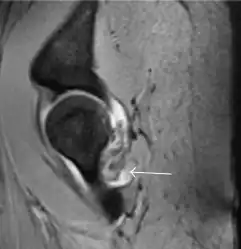

Most of the angles and measurements described in the plain radiograph section can be accurately reproduced on MRI. In addition, the superiority of MRI resolution with intra-articular contrast allows detection of labral and chondral abnormalities that may influence the choice of medical, percutaneous, or surgical management (Figure 9).[1]

Figure 9:

Sagittal T1 weighted image showing anterosuperior labral tear.[1]

Sagittal T1 weighted image showing chondral lesion.[1]

Sagittal CT-arthrography showing posteroinferior chondral injury.[1]

Coronal CT-arthrography (d) showing ligamentum teres tear.[1]

MR arthrography has proven superior in accuracy when compared to native MR imaging. It is considered the best technique to assess the labrum. Knowledge of the normal variable morphology of the labrum helps to differentiate tears from normal variants. A triangular shape is most commonly seen in 66% of asymptomatic volunteers, but round, flattened, and absent labra can also be found in asymptomatic populations. MR arthrography has demonstrated sensitivity over 90% and specificity close to 100% in detecting labral tears. Loose bodies are demonstrated as filling defects surrounded by the hyperintense gadolinium.[1]

Association between labral tears and chondral damage has been demonstrated. This underscores the interaction between cartilage and labrum damage in the progression of osteoarthritis. Chondral damage to the posteroinferior part of the acetabulum as a contrecoup lesion occurs in approximately one-third of pincer cases secondary to persistent abutment on the anterior part of the joint leading to a slight posteroinferior subluxation. This is considered a bad prognosis sign.[1]

MR arthrography can also demonstrate ligamentum teres rupture or capsular laxity, which are debated causes of microinstability of the hip. Elongation of the capsule or injury to the iliofemoral ligament or labrum may be secondary to microtrauma in athletes. MR can demonstrate abnormalities in these cases, such as increased joint volume or a ligamentum teres tear (Figure 9).[1]